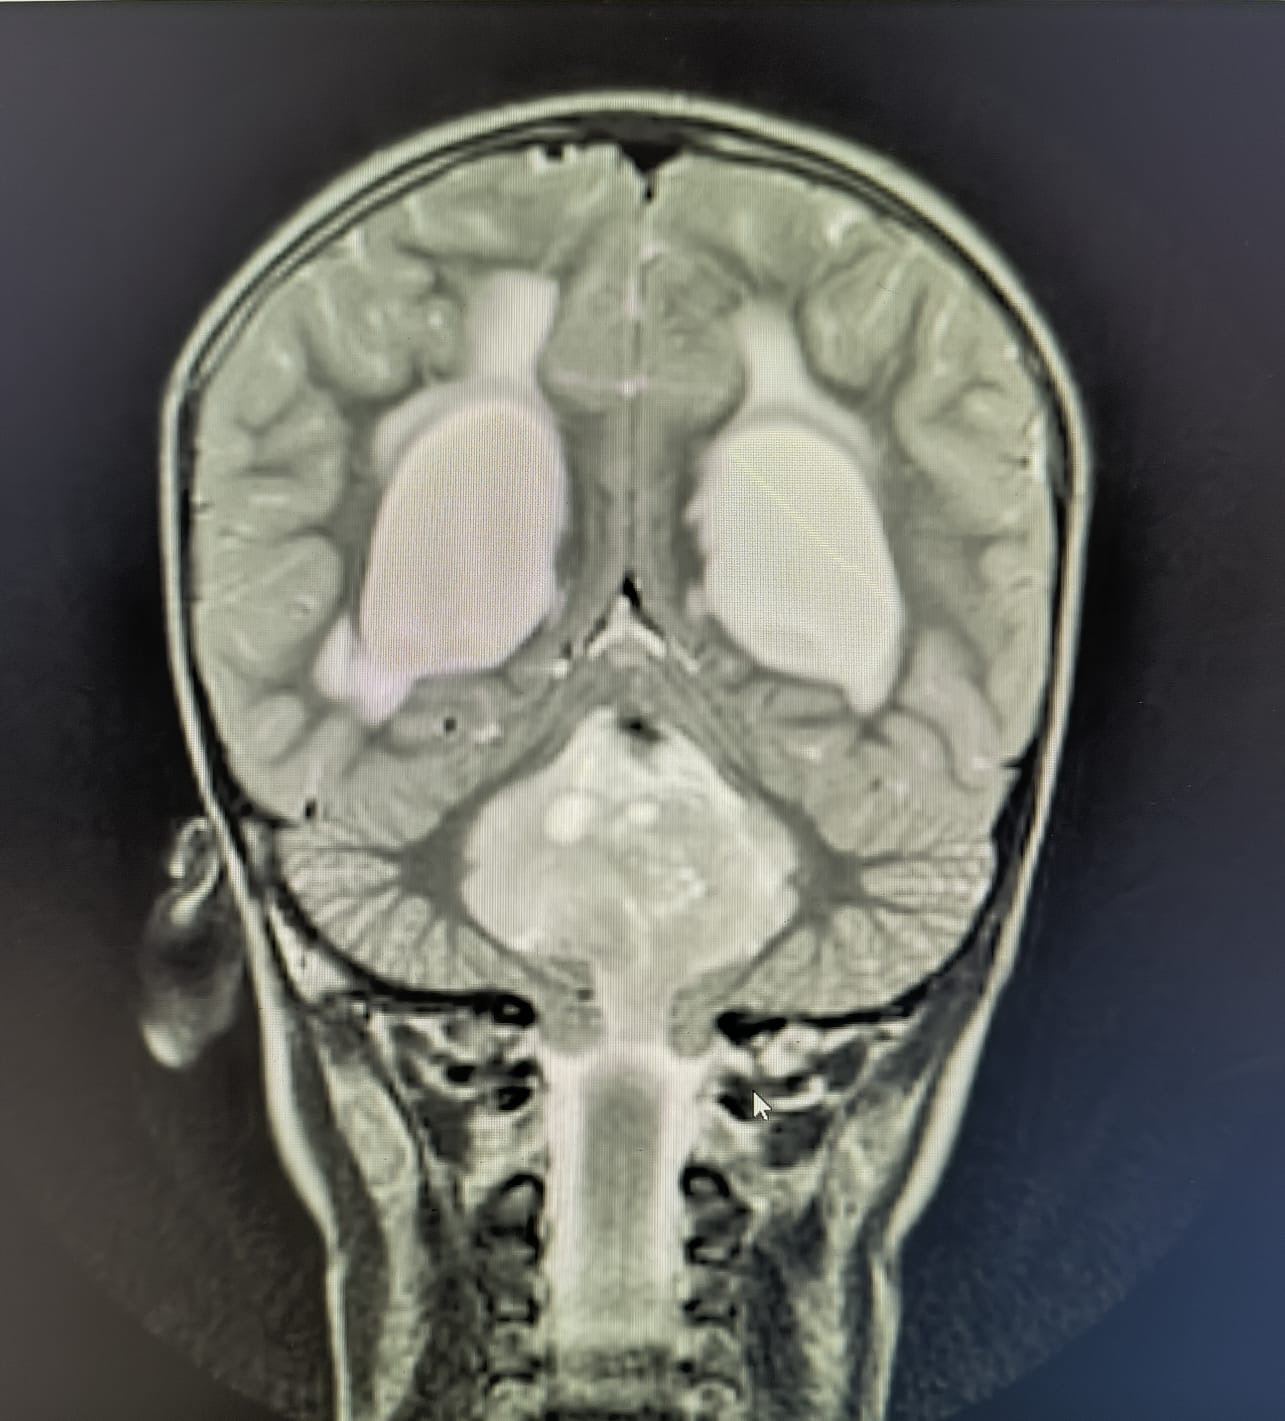

في سابقة هي الأولى من نوعها، تمكن فريق طبي متخصص في مستشفى الكرك الحكومي من إجراء عملية جراحية معقدة لإزالة ورم من رأس طفل. وقد تكللت العملية بنجاح، مما أدخل البهجة والسرور على قلب عائلة الطفل وكافة الكوادر الطبية في المستشفى.

وقاد العملية الاستشاري في جراحة قعر الجمجمة، الدكتور عامر العمري، بمساعدة فريق متكامل من الأطباء، الدكتور نضال أبو سدره والدكتور يوسف أبو نواس. استغرقت العملية نحو عشر ساعات، حيث تم استخدام تقنيات حديثة ودقيقة لضمان إزالة الورم بأمان ودون التأثير على الأنسجة المحيطة.